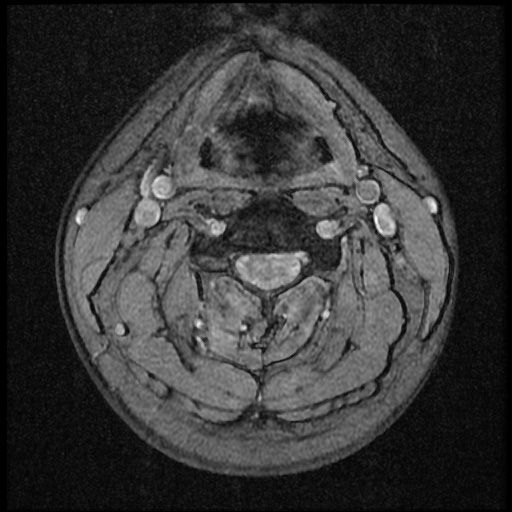

이 MRI 사진은 21년도 사고 당시 찍은 MRI 사진 입니다. 확인 부탁드립니다~

전체 mri를 다 봐여겠지만 보여주신 mri 컷에서는 의미있는 경추 디스크탈출이 보이지 않습니다.